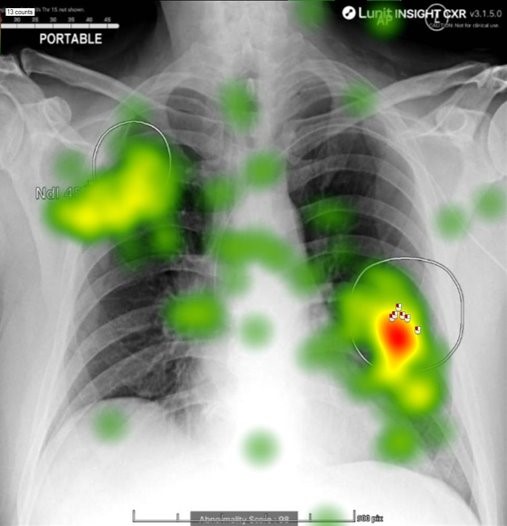

The theme of trust in AI came up repeatedly throughout the summer school and it connected directly with my own research. I had an opportunity to present my work on the role of confirmation bias during an AI-assisted medical image interpretation task, the main aim of which is to investigate whether confirmatory AI output influences user perceptions of system reliability and subsequent reliance on AI. Attendees were particularly interested in the use of eye-tracking technology to highlight changes in visual search behaviour when interacting with AI. For example, the presence of an AI prompt may lead the observer to neglect other regions of the image. This may be beneficial if the prompt has correctly identified a suspicious region but detrimental if AI misses an important finding. Studying these human factors is essential if AI integration in clinical decision-making is to be both safe and effective.